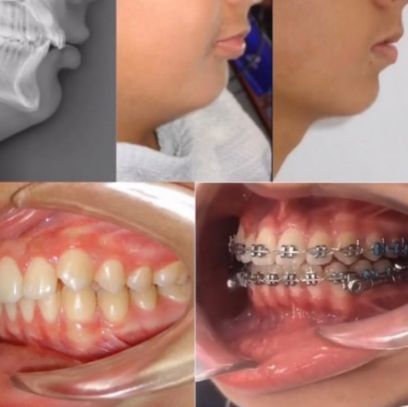

НАШИ РАБОТЫ УСТАНОВКИ СИСТЕМЫ БРЕКЕТОВ